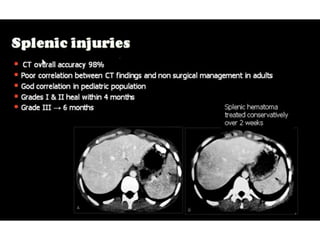

This document discusses the spleen and causes of splenomegaly (enlarged spleen). It begins by thanking radiologists for their assistance. Simple cyst criteria are outlined. Splenogonadal fusion and sarcoidosis are mentioned. The main causes of splenomegaly are then listed, including infections, portal hypertension, hemolytic anemias, hematological malignancies, infiltrative disorders, collagen vascular disorders, and congestive cardiac failure.